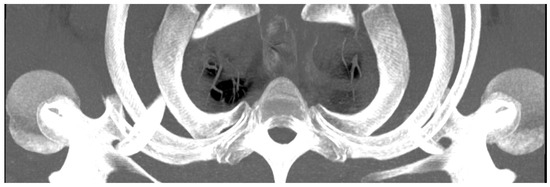

| Variable Name | Abbreviation | Description |

|---|---|---|

| Anterior to posterior rip extension | RAP | From the most ventral point of the caput costae 1, a perpendicular line to the tangent of the posterior edge of the first thoracic vertebral body. |

| Vertebral body width | VBW | Width of the first vertebral body at the level of the centre of the articulatio capitis costae 1 |

| Vertebral body depth | VBD | From anterior edge to posterior edge (most ventral point of vertebral foramen) of the first vertebral body |